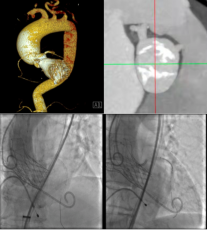

【一院·技术】心脏换瓣不开胸,济宁市第一人民医院心内科完成高难度二叶式主动脉瓣重度狭窄TAVR术

高龄老人基础疾病较多,身体弱无法承担开胸手术怎么办?近日,济...